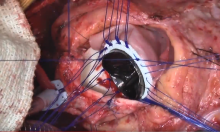

An eight-year-old girl who had prior repair of atrioventricular septal defect underwent multiple prior reoperations, including repair and subsequent mechanical left AV valve replacement. Her current problem was shortness of breath with patient prosthesis mismatch, severe aortic regurgitation with left ventricular fibromuscular outflow tract obstruction, and severe tricuspid regurgitation. Through a fourth-time redo sternotomy, the authors performed a left AV valve re-replacement with a 19 mm St Jude mechanical valve, a Konno aortoventriculoplasty using a 19 mm Onyx mechanical valve, and an eccentric banded tricuspid annuloplasty. Separation from bypass was uneventful, with normal hemodynamics and sinus rhythm.

The patient was extubated the night of surgery and was discharged on postoperative day seven without complications. A predismissal echocardiogram revealed a mean gradient of 17 mm Hg across the aortic prosthesis, and a mean gradient of 7 mm Hg across the mitral prosthesis. Her heart rate was 106 beats/min and hemoglobin was 9.4 g/dL. The mean diastolic gradient across the tricuspid valve was 4 mm Hg with trivial regurgitation.